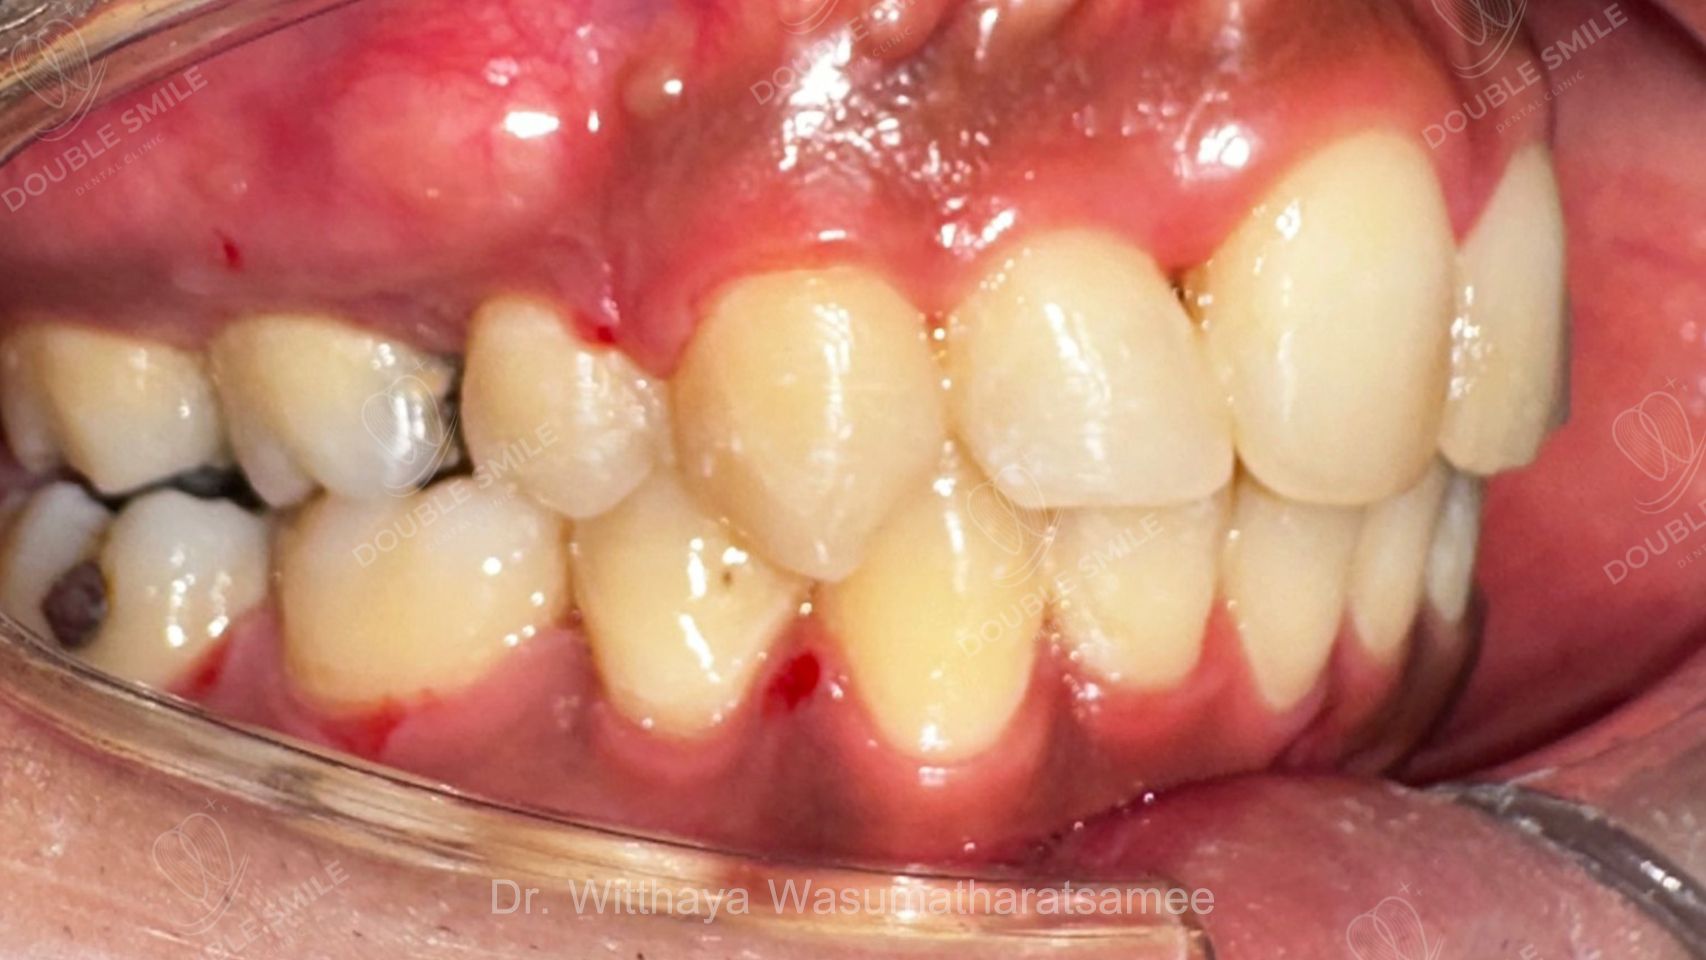

Before

Case Review

Before & After